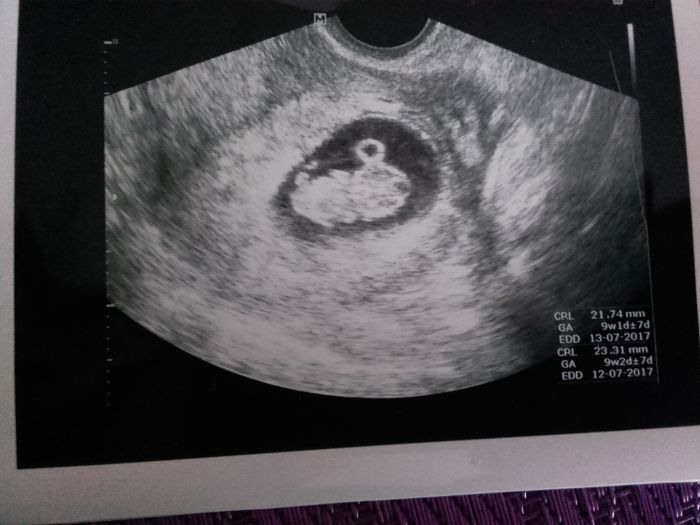

Tak se hlásím z kontroly. Dopadlo to dobře. Srdíčko jsem slyšela. Prdísek mi zamával a i nožičkama mrskal. Vypada to o den mladsi nez podle MS. Mám samozřejmě nařízený klid fyzicky i psychický vzhledem k minulosti. Doktorka řekla že zatim ještě nejásáme ale trochu už se radujeme